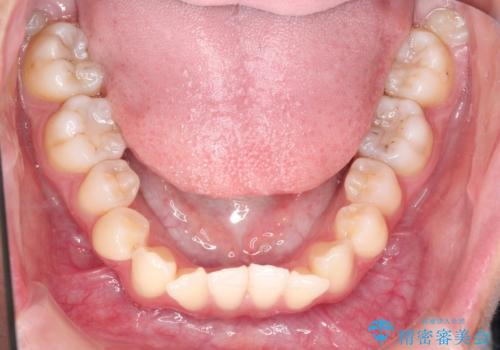

インビザラインによる非抜歯矯正 ガタガタな歯並びを整った歯並びへ

- 前歯のガタガタを主訴に来院されました。

抜歯矯正も考えられる状態でしたが、非抜歯矯正を希望されました。

使用時間を守っていただけたので、スムーズに治療を終わることができました。